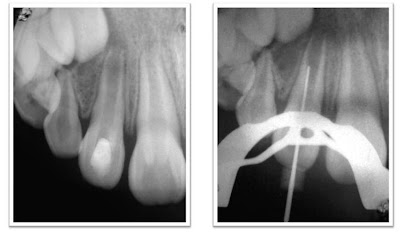

| Radiografía pre operatoria Radiogrtafía conductometría |

| Radiografía Post Operatoria |

| Radiografía pre operatoria Radiografía conductometría |

| Radiografía post operatoria (toma ortoradial y toma distoradial) |